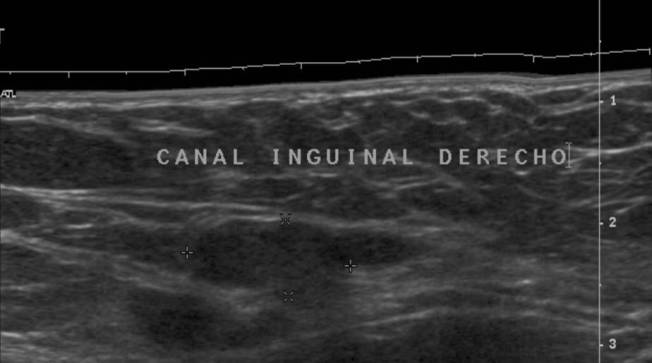

5.3.1 Criptorquidia:

En el séptimo mes de gestación los testículos descienden del abdomen al escroto.

La mayoría de los testes no descendidos se encuentran en el canal inguinal

Se asocia en edad adulta con malignización, torsión e infertilidad.

Técnica exploratoria:

Con una sonda de alta frecuencia buscaremos los testes en las bolsas escrotales, si no estuviesen situados en su lugar iríamos recorriendo canal inguinal hasta encontrarlos.

Habitualmente se hallan en el canal inguinal, bajo una lamina de grasa, podemos, con la manipulación hacer que el teste caiga a la bolsa escrotal.

5.3.1 Cryptorchidism:

In the seventh month of gestation, the testicles descend from the abdomen to the scrotum.

Most undescended testes are found in the inguinal canal

It is associated in adulthood with malignancy, torsion and infertility.

Exploratory technique:

With a high frequency probe we will look for the testes in the scrotal bags, if they were not in place we would go through the inguinal canal until we found them.

Usually they are in the inguinal canal, under a sheet of fat, we can, with the manipulation to make the test fall into the scrotal sac.